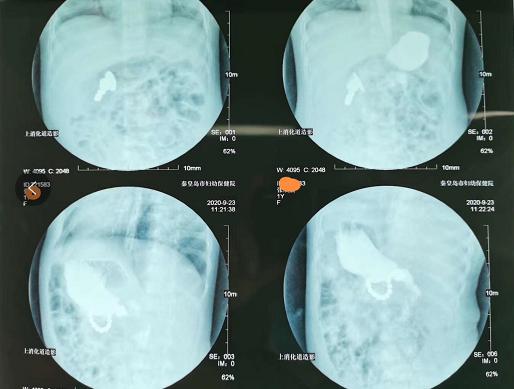

住院后为了进一步了解异物的位置,丁岩医生带着囡囡作了泛影葡胺的上消化道造影检查,发现硬币在胃窦部,而粘结的磁力珠在肠道,由于病史长达一个月,科主任孙立宝考虑存在磁力珠压迫胃肠道的部位有坏死穿孔的可能,决定先行腹腔镜探查,无法取出时再开腹手术。